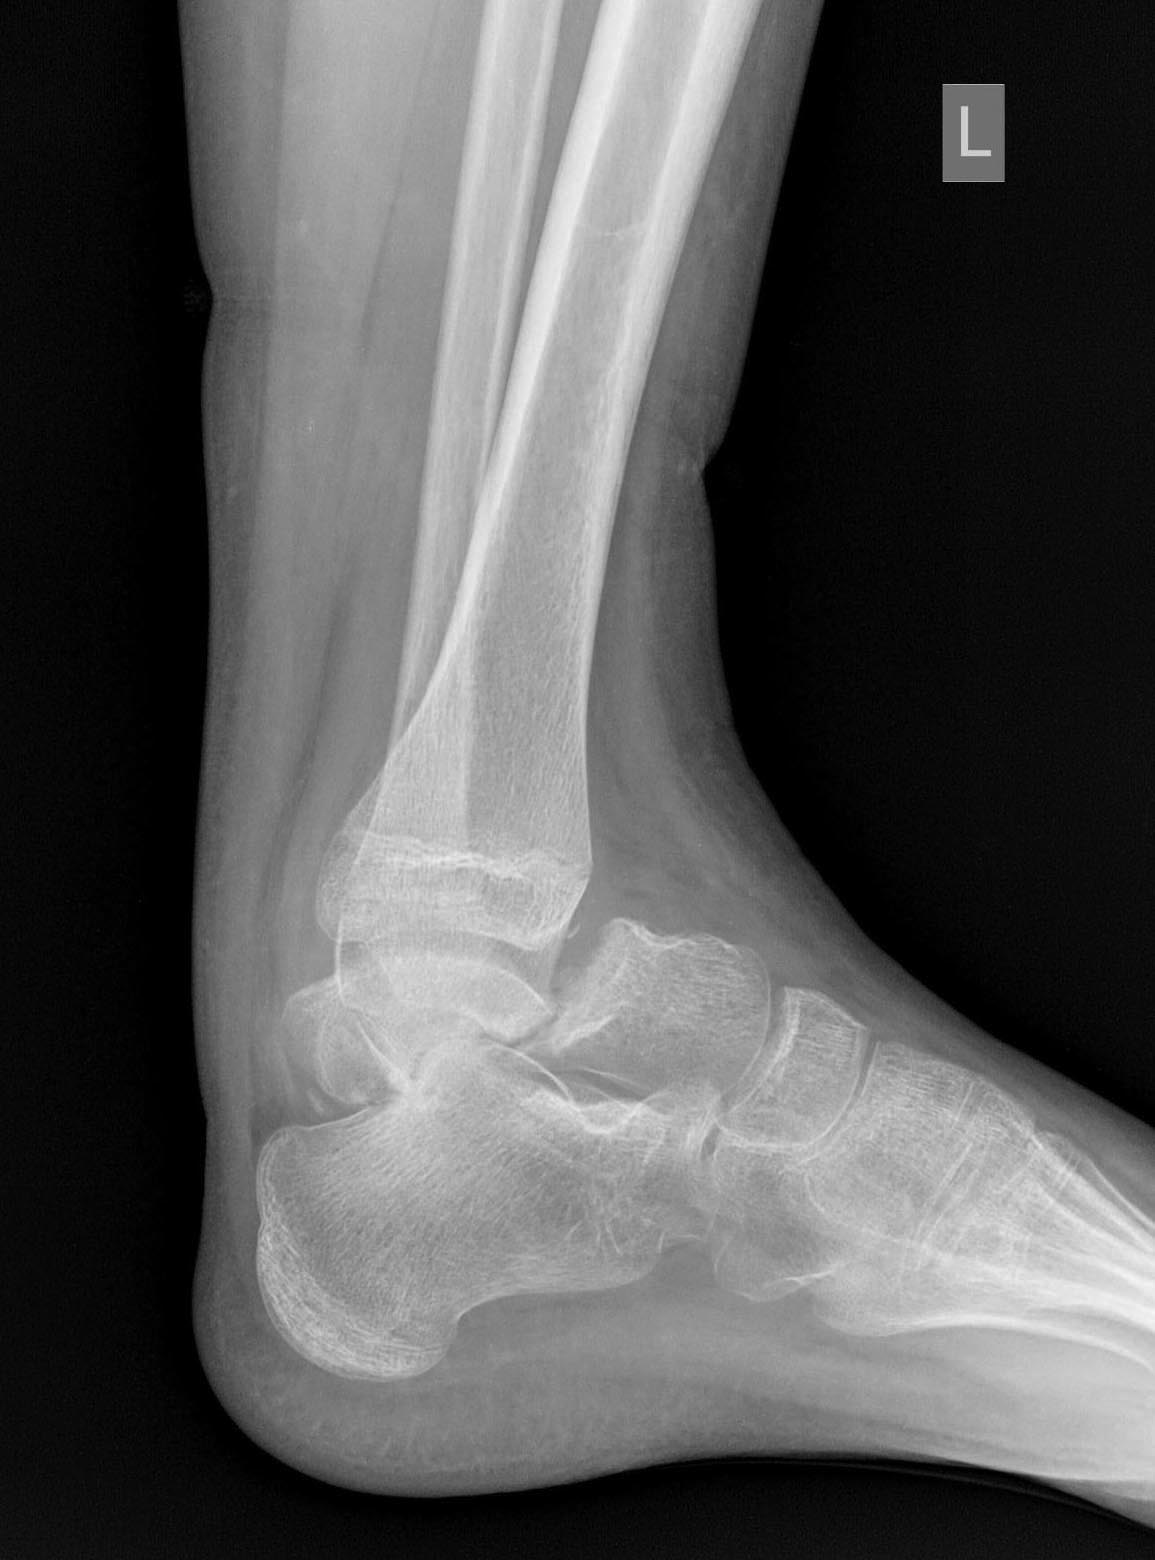

Нелеченный перелом шейки таранной кости у 14-летнего подростка

Травма 2 мес. назад. На снимках перелом шейки таранной кости в детской больнице не увидели.

Сказали, мол, растяжение - наступай. Ну вот он и наступает. Сейчас ходит с тростью.

Что делать? Подтаранный артродез с gjgsnrjq сохранить голеностопный сустав, или большеберцово-пяточный блок с использованием остатка таранной кости в качестве трансплантата?

A boy 14 was referred yesterday.

Injured 2 mnth ago, the fracture was missed somewhere, and he was recommended to walk. And he was trying to do this all that time. Now he is able to walk with cane.

Either subtalar fusion with attempt of ankle preservation, or tibio-calcaneal fusion with the use of remnant of the talar dome as a graft?

How would you manage this case?